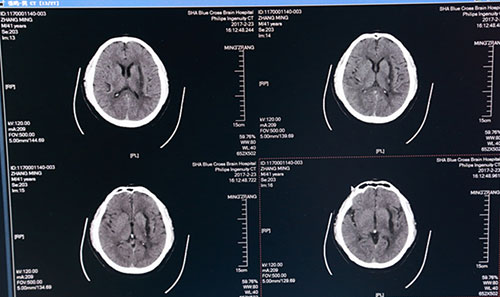

术后一周头颅CT:血肿术后改变,血肿清除干净

全脑血管造影(DSA)图像:红圈内为出血部位,血管未见异常

术后第二日,复查头颅CT示:左侧基底节区血肿已基本清除干净,术后一周再次复查头颅CT示:左侧基底节区血肿术后改变,血肿已基本清除,蛛网膜下腔渗出较前减少,金属引流管撤除;术后一月复查全脑血管造影(DSA),出血点血管未见异常,排除脑动脉瘤破裂出血可能。目前患者精神奕奕,正在积极接受康复综合治疗,不日即可出院,回归正常生活。